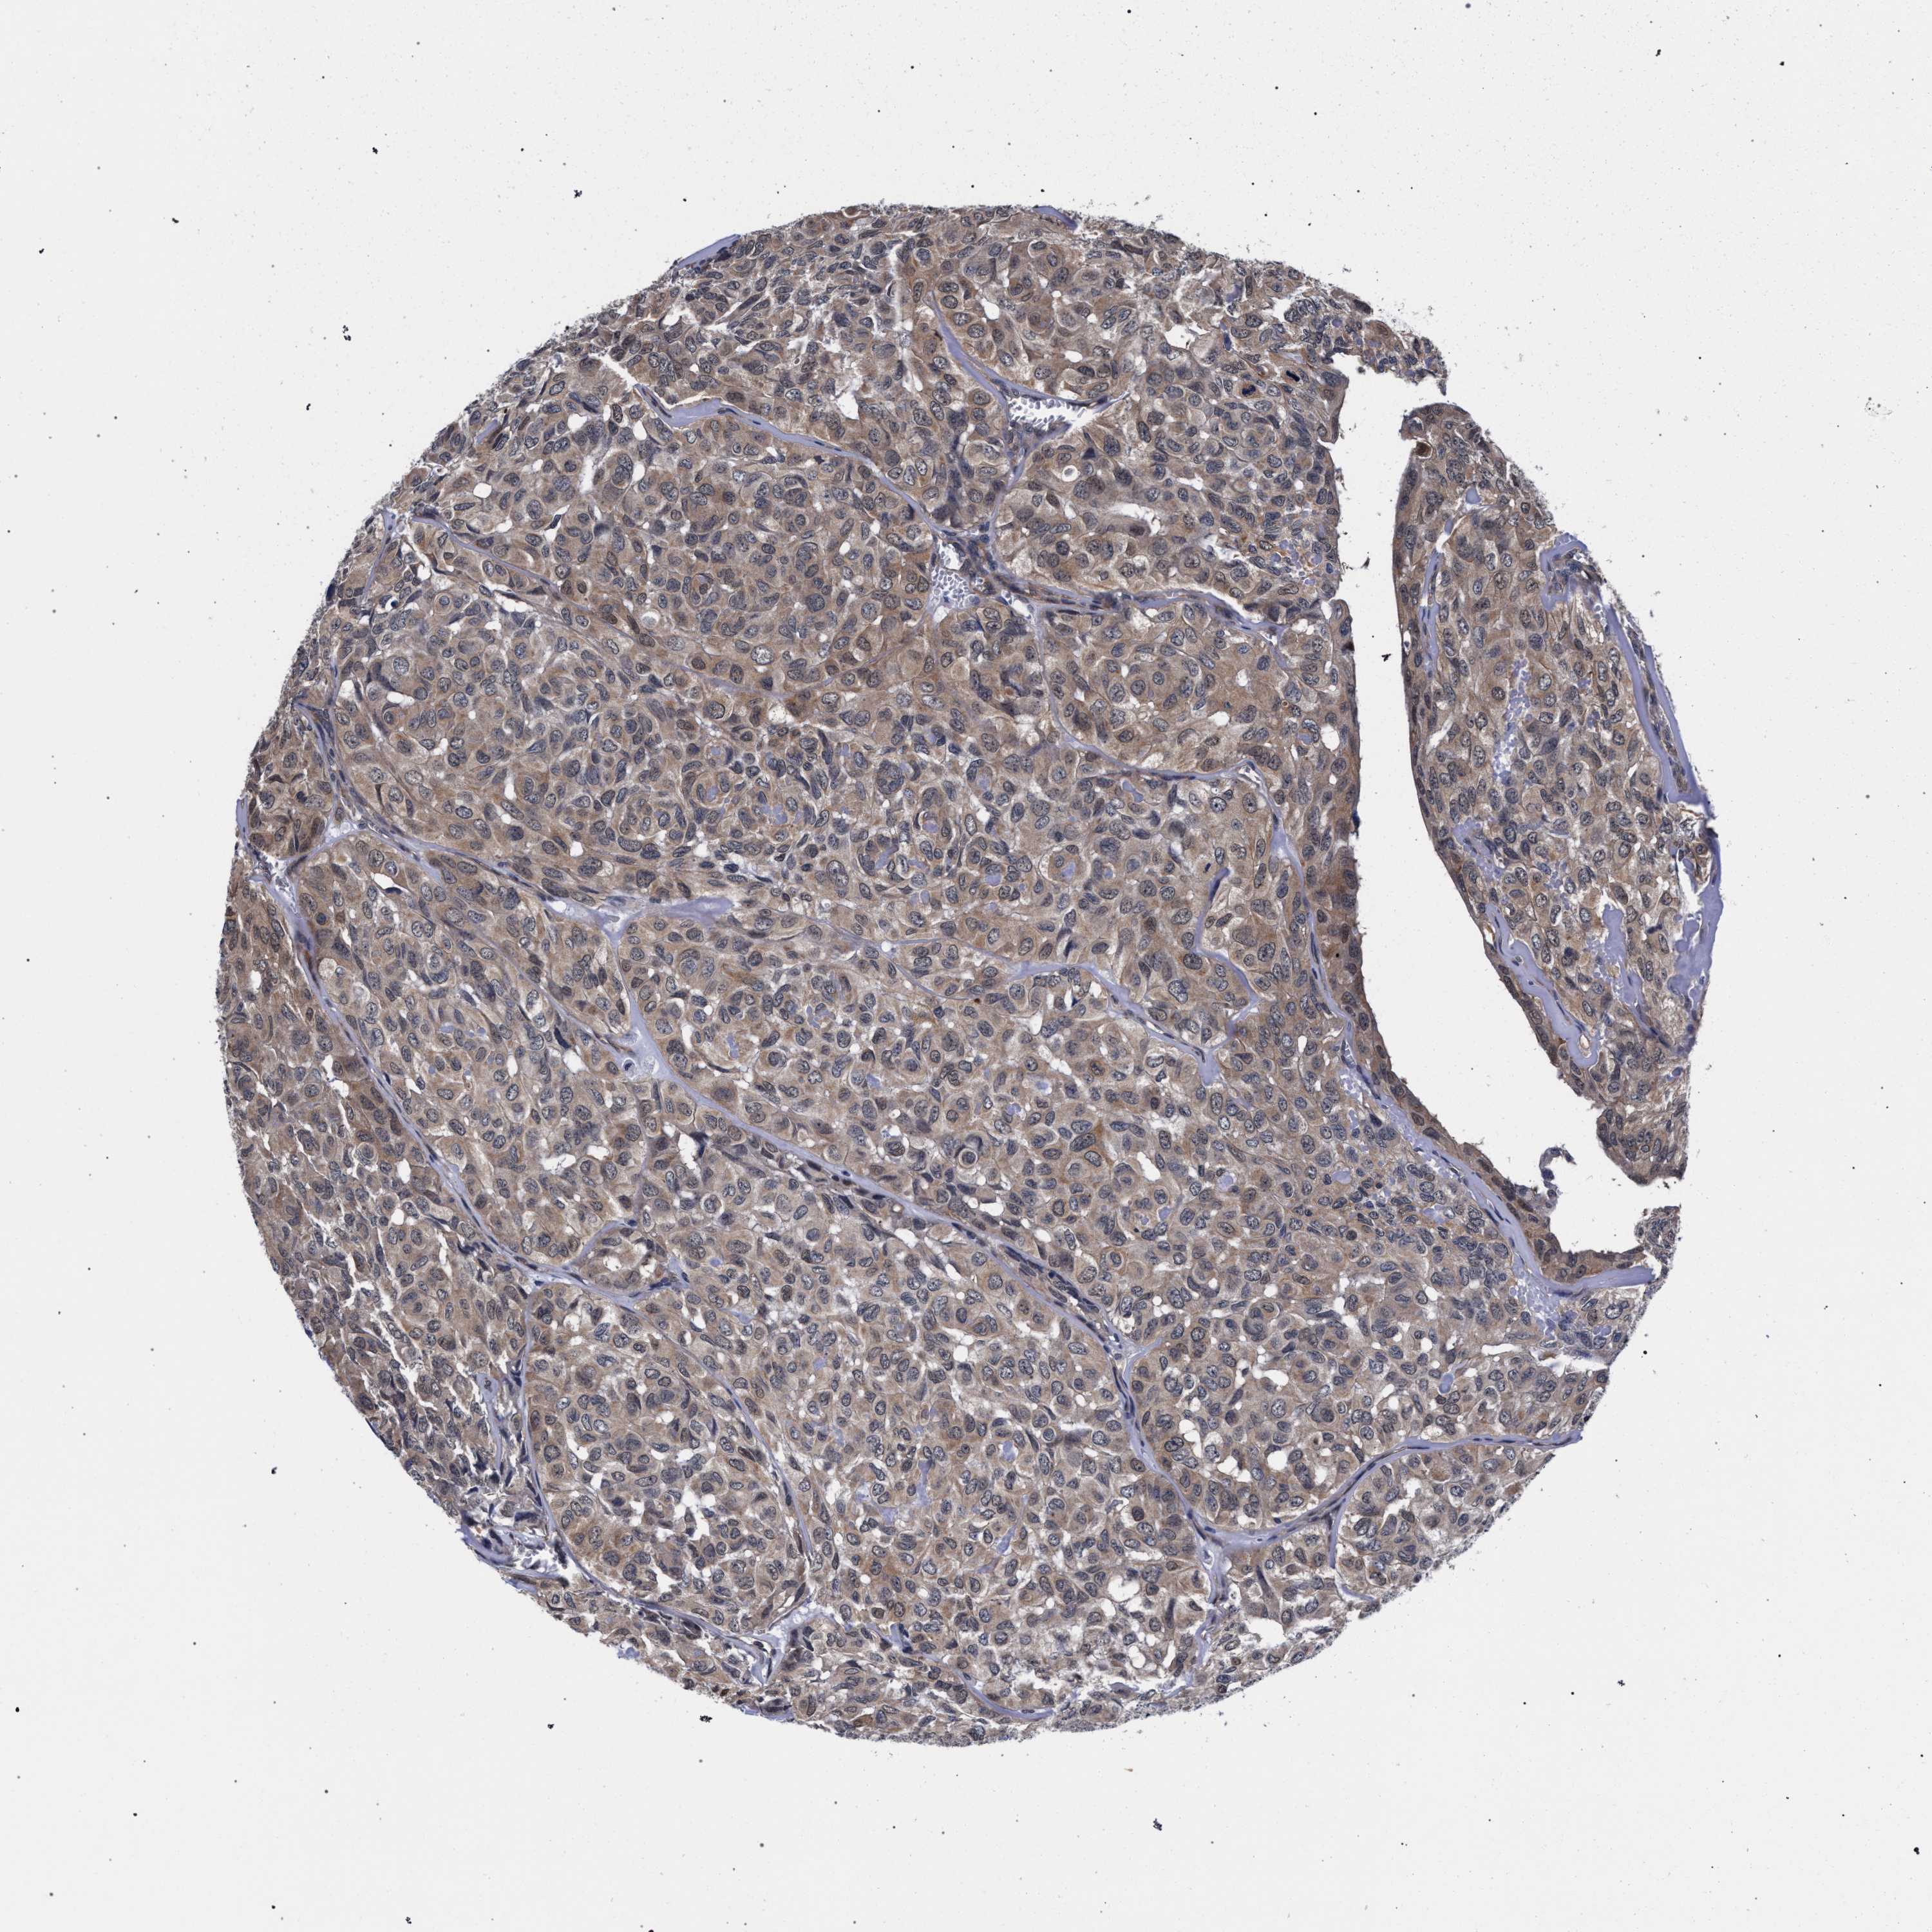

HEAD AND NECK CANCER - Protein expressioni

A mouse-over function shows sample information and annotation data. Click on an image to view it in a full screen mode. Samples can be filtered based on level of antibody staining by selecting one or several of the following categories: high, medium, low and not detected. The assay and annotation is described here.

Antibody stainingi

Antibody staining in the annotated cell types in the current human tissue is reported as not detected, low, medium, or high, based on conventional immunohistochemistry profiling in selected tissues. This score is based on the combination of the staining intensity and fraction of stained cells.

Each image is clickable and will lead to virtual microscopy that enables deeper exploration of all samples and also displays staining intensity scores, fraction scores and subcellular localization as well as patient and tissue information for each sample.

Antibody HPA019232

Antibody HPA021497

Antibody HPA021768

Staining

High

Medium

Low

Not detected

Intensity

Strong

Moderate

Weak

Negative

Quantity

>75%

75%-25%

<25%

None

Location

Nuclear

Cytoplasmic/membranous

Cytoplasmic/membranous,nuclear

Squamous cell carcinoma, NOS

Squamous cell carcinoma, metastatic, NOS

Adenocarcinoma, NOS